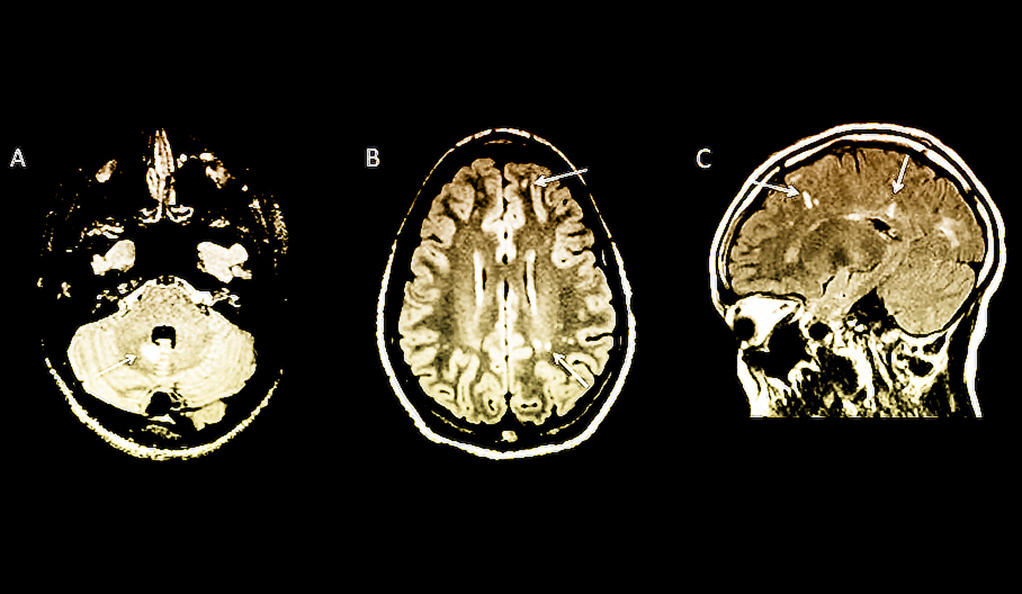

Examples of typical MS MRI findings Download Scientific Diagram Can Ms Be Diagnosed Without An Mri At this time, no symptoms, physical findings or laboratory tests can, by themselves, prove that you. the number of lesions on an initial mri of the brain (or spinal cord) can help assess your risk of developing a second attack in the. magnetic resonance imaging (mri) is crucial in the diagnosis and management of multiple sclerosis (ms). Learn. Can Ms Be Diagnosed Without An Mri.